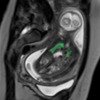

Congenital Diaphragmatic Hernia

A study is

starting on the possibility of predicting the occurrence of pulmonary

hypertension (PH) in the newborn from fetus radiomics features in MRI.

As PH is related to the need of ECMO (ExtraCorporeal Membrane

Oxygenation) for the newborn, early prenatal assessment may be vital

for therapy. Collaboration with the group of G. Cavallaro MD PhD from

Fondazione IRCCS Ca' Granda Ospedale Maggiore Policlinico, Università

degli Studi di Milano.